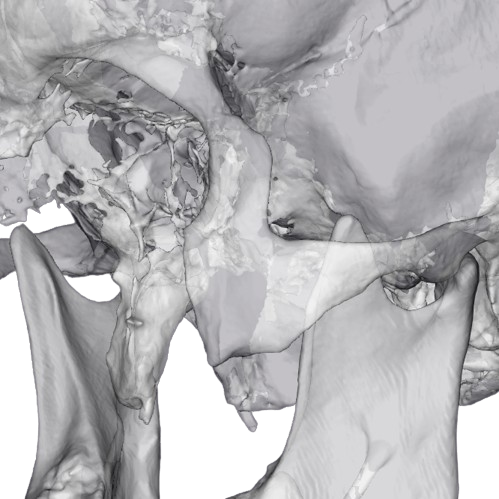

Об’єм: 16×8 см

1200 ₴

Призначається для виявлення дегенеративно-дистрофічних і деструктивних змін на різних стадіях.

Записатися Детальніше

Об’єм: 16×8 см

1000 ₴

Призначається для виявлення дегенеративно-дистрофічних і деструктивних змін на різних стадіях.

Записатися Детальніше

Об’єм: 8×8 см

800 ₴

Призначається для виявлення дегенеративно-дистрофічних і деструктивних змін на різних стадіях.

Записатися Детальніше

Об’єм: 8×8 см

600 ₴

Призначається для виявлення дегенеративно-дистрофічних і деструктивних змін на різних стадіях.

Записатися Детальніше